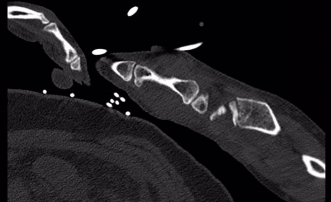

术后第一天,患者意识恢复清醒,复查头部CT提示颅内血肿清除彻底。全腹CT、双腕关节CT显示:肠管管壁明显水肿增厚,邻近肠系膜肿胀,肠间隙模糊,盆腔少量积液,腹腔内未见游离积气,提示肠管或肠系膜损伤;右侧月骨脱位,左侧桡骨远端骨折。

胃肠小儿外科、脊柱创伤外科会诊讨论,确定了分期治疗方案。术后第2天,胃肠小儿外科张达主任医师在全麻下为患者行小肠破裂修补术+腹腔脓肿清除术+肠粘连松解术+肠排列术。脊柱创伤外科薛建康主任医师为患者行左侧桡骨骨质手法复位后石膏外固定,后行右月骨脱位切开复位。

(月骨脱位) (固定术后)